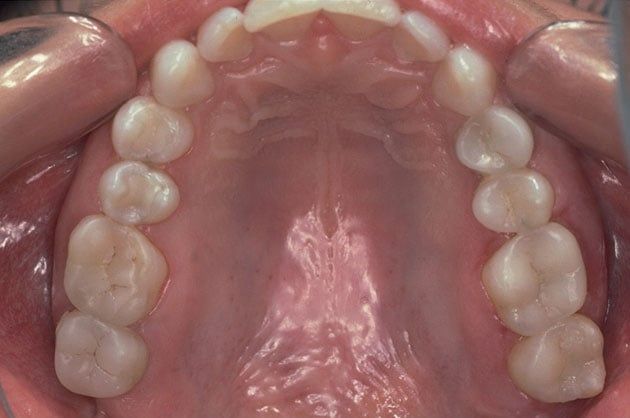

Tooth-colored fillings, white fillings and composite resin fillings are all names for the high-strength, natural-looking fillings that can be placed today instead of silver or gold (also known as amalgam fillings). No matter what the name, Fresh Smile Dental Practice will know just what you're talking about when referring to this natural-looking filling.

Composite fillings are today's modern filling choice. They are made to match your tooth's natural color to make them virtually invisible to notice and are placed onto the tooth by bonding the filling material to the tooth so they do not have the unlikely chance of falling off. Many patients choose to replace their old silver and gold fillings with composite fillings.

White fillings are made from a high-strength composite resin that can be easily color-matched to your natural tooth making it nearly invisible to you and anyone else. Unlike silver and gold fillings, composite tooth-colored fillings actually bond to the tooth which means they support the surrounding tooth structure, which helps to prevent breakage and insulate the tooth from excessive temperature changes. You are much less likely to have a composite filling fall out which is a common issue with metal fillings.